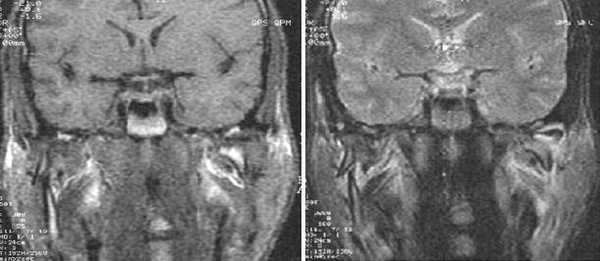

После вмешательства пациенты оставались на сутки под наблюдением врача в стационаре одного дня. В ближайшем послеоперационном периоде назначались антибиотики и обезболивающие средства. У всех оперированных пациентов после артроскопии положение суставного диска нормализовалось, но сразу после операции движения нижней челюсти в полном объеме отмечены только у 4 пациентов, а у остальных потребовались реабилитационное лечение, включающее физиопроцедуры и механотерапию. Косметических дефектов у пациентов после артроскопии не наблюдалось (рис. 4). Рисунок 4. Внешний вид области вмешательства через 36 сут (а)после артроскопии. Рисунок 4. Внешний вид области вмешательства через 60 сут (б) после артроскопии.